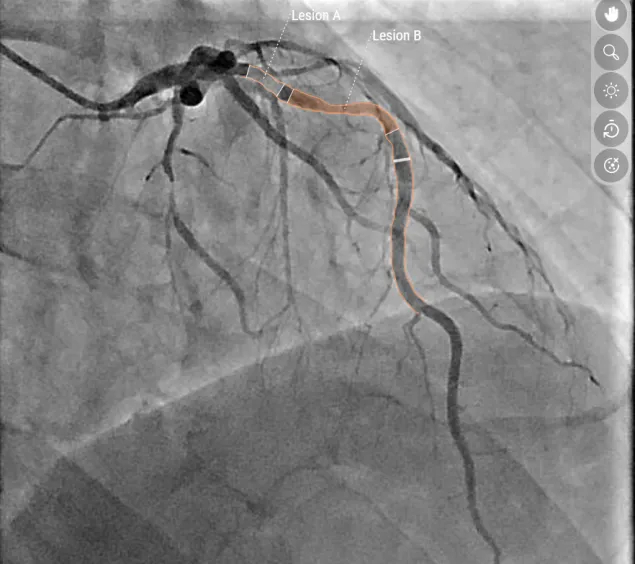

Bildaufnahme einer Engstelle der Vorderwand des Herzens

Darstellung von Engstellen der Vorderwand des Herzens

Links die klassische Darstellung, rechts das KI-Modell: Mit Hilfe der Software konnten zwei Engstellen an der Vorderwand des Herzens identifiziert und eine relevante Beeinträchtigung der Sauerstoffversorgung festgestellt werden. Das hämodynamische Modell zeigt: Eine gezielte Aufdehnung nur einer der beiden Stenosen reicht aus, um den Blutfluss wieder zu normalisieren.